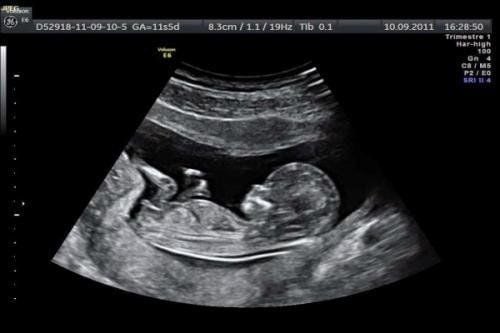

Xét nghiệm sàng lọc tiền sinh không xâm lấn (Non – invasive prenatal testing, NIPT) sử dụng DNA tự do hay còn gọi là DNA ngoại bào (cfDNA) trong máu mẹ có độ nhạy và độ đặc hiệu rất cao khi sàng lọc các bất thường như tam nhiễm sắc thể 21, 18 và 13. Trong những nghiên cứu lớn độ nhạy cho các loại tam nhiễm sắc thể 21, 18 và 13 lần lượt là 99,7%, 97,9% và 99%, trong khi tỷ lệ dương tính giả (false – positive rate FPR) chỉ 0,04% cho mỗi loại tam nhiễm sắc thể. Bên cạnh đó với nhóm đơn nhiễm sắc thể X (monosomy X – Hội chứng Turner) có độ nhạy chỉ 95,8% và tỷ lệ dương tính giả là 0,14%. Với những thông số trên, NIPT là một xét nghiệm sàng lọc có độ chính xác rất cao. Tuy nhiên, NIPT vẫn chỉ là xét nghiệm sàng lọc và không thể thay thế cho xét nghiệm chẩn đoán.